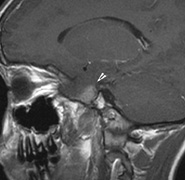

Fig. 6. Surveillance images of a 12-year-old girl with NF1 and an optic nerve glioma which has extended to involve the chiasm. Pre- (a) and postcontrast (b) T1-weighted coronal images reveal a large suprasellar mass with an enhancing component (arrow) seen separately from the normally enhancing pituitary gland. (c) Axial scans through the suprasellar cistern show the tumor is high signal on T2-weighted scans. (d) Enlargement of the chiasm, optic nerve and hypothalamus is visible on the post-contrast T1-weighted sagittal image. Although optic nerve glioma usually has a good prognosis (with visual function often remaining stable in the absence of any intervention66,67), chiasmal involvment is a poor prognostic indicator. A sign of chiasmal involvment may be new onset of endocrine disorders or nystagmus. Surgical excision of chiasmal gliomas carries a high risk of visual loss.68–70